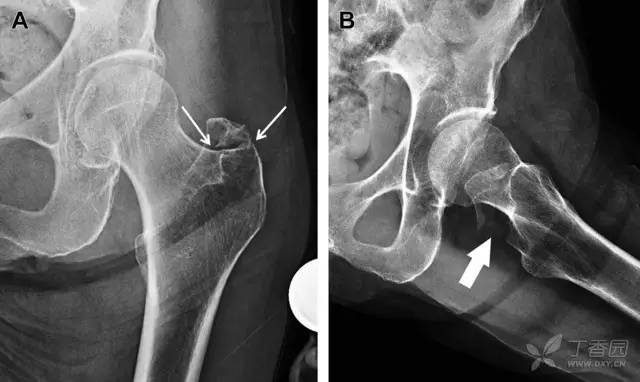

股骨颈骨折常发生在老年人,头下型骨折最常见,但是当股骨外旋或有明显的关节炎骨赘形成时,骨折较难发现。此外,肥胖和骨量减少增加髋部 X 片诊断难度,所以需格外关注。

因骨结构重叠影响,股骨转子骨折发生轻度移位时亦很难发现,加做一个不同角度的 X 线片有助于诊断(图 7)。

图 7 摔倒后股骨大转子骨折。A 正位片初步检查未发现明显骨折,进一步检查发现大转子上方皮质中断(箭头)。B 蛙式侧位片示骨折分离,尤其是后方(箭头)。初步检查时忽视了这一点,是因为股骨颈未能充分显示